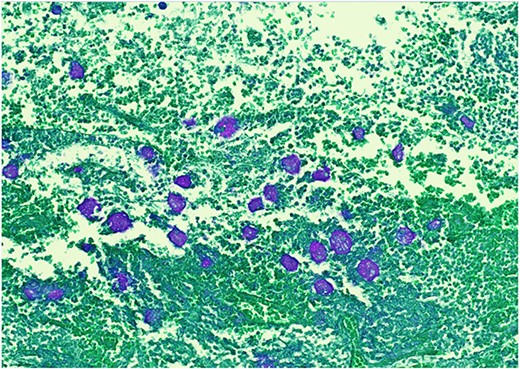

Pathology resulted on post-operative day three showing an inflamed appendix, 1.4 cm in diameter, with an exudative-filled lumen. On microscopic stains, there was evidence of acute appendicitis with frequent scattered unicellular organisms within areas of ulcerated appendiceal mucosa and submucosa (Figs 6 and 7). These cellular forms have round cell membranes, single prominent round eosinophilic nuclei and foamy cytoplasm (Fig. 5). Occasional forms show evidence of erythrophagocytosis (Fig. 3). Forms were also highlighted by trichrome and PAS special stains (block A1) and were negative for CD68 (a marker of macrophages; block A1) (Figs 2–4). These morphologic features are most consistent with E. histolytica, which is a pathogenic parasite in the lower GI tract, and likely the causative agent for acute appendicitis in this case.

H&E 200X—unicellular parasites within submucosal tissue with inflammation.